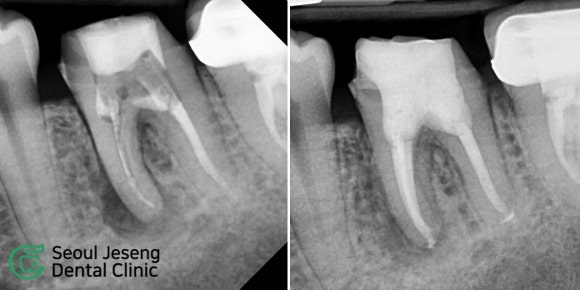

[치료사례] 재신경치료 (1)

#신촌치과 #재근관치료 #현미경신경치료 #치과보존과전문의 #서울재생치과